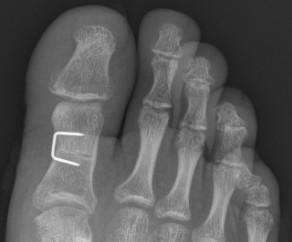

Chevron osteotomy +/- DSTP

Indications

- incongruent joint

- mild hallux valgus: HVA < 30o / IMA < 15o

Technique

60° osteotomy apex distal

- apex 1 cm from articular surface

- longer plantar limb to avoid sesamoids and inferior joint surface

Translation

- 5 mm medial

- 1mm displacement corrects IM angle 1º

- can perform medial closing wedge to correct DMMA

Fixation

- sutures / k wire / screw

Closure

- imbricate medial capsule